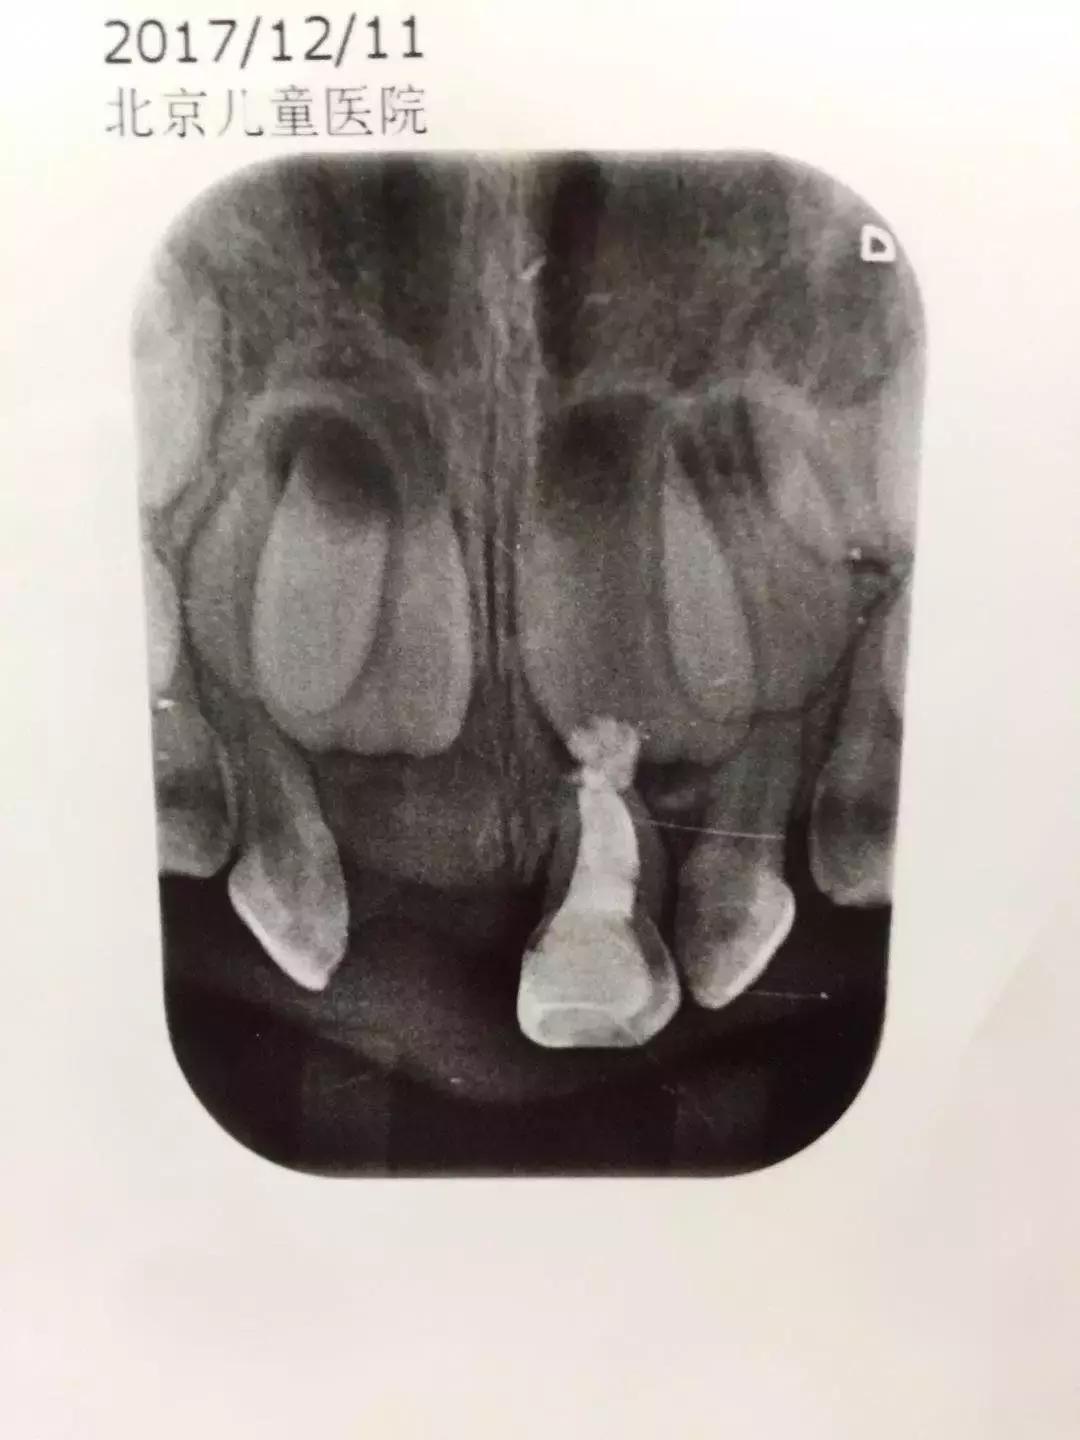

这个是多多的牙片,上面是目前隐藏在牙龈里的恒牙,现在拔了坏掉的龋齿,就等着恒牙萌出来。长出来前娃就要一直是“一颗牙门神”的状态了,心塞